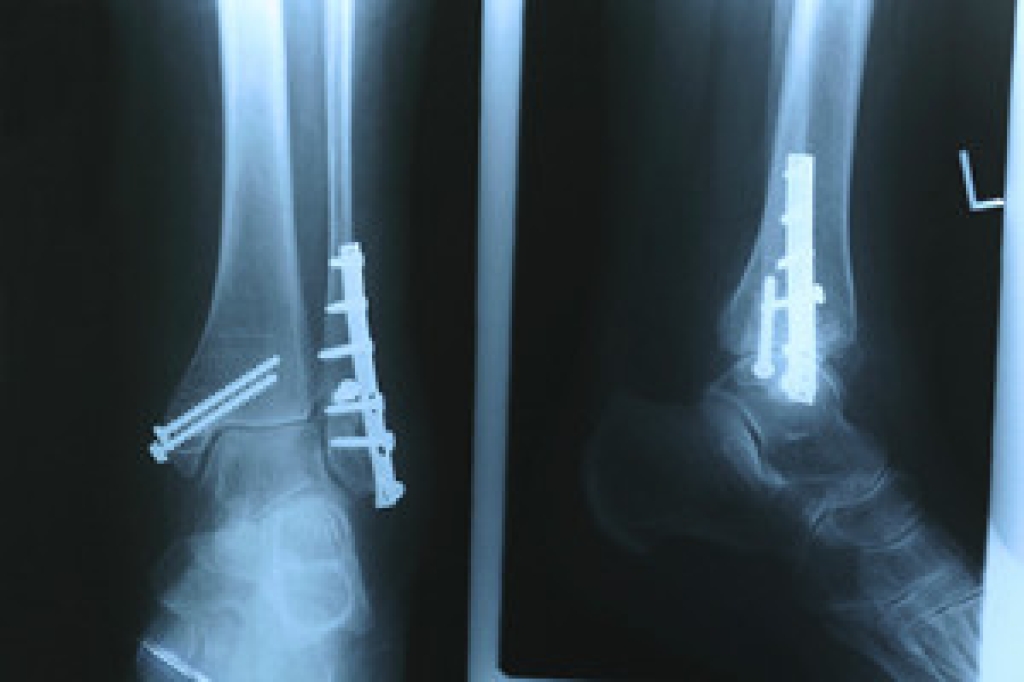

Sports related injuries are commonly treated using the RICE method. This includes rest, applying ice to the injured area, compression and elevating the ankle. More serious sprains and injuries may require surgery, which could include arthroscopic and reconstructive surgery. Rehabilitation and therapy may also be required in order to get any recovering athlete to become fully functional again. Any unusual aches and pains an athlete sustains must be evaluated by a licensed, reputable medical professional.